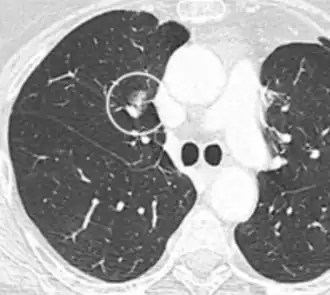

- Location: Upper lobe location is a risk factor for cancer, while a location close to a fissure or the pleura indicates a benign lymph node,[8] especially if having a triangular shape.[9]

- Margin morphology: a spiculated margin is a risk factor for cancer.[8] Benign causes tend to have a well defined border, whereas lobulated lesions or those with an irregular margin extending into the neighbouring tissue tend to be malignant.[10] In particular, spiculations are highly predictive of malignancy with a positive predictive value up to 90%.[9] Also, a "notch sign", which is an abrupt indentation of the nodule, increases the risk of cancer, but may also be found in granulomatous diseases.[9]

-

subpleural nodule.[9] -

Round well-delineated solid lung nodule with smooth border.[9] -

Lobulated nodule.[9] -

Spiculated lung nodule.[9] -

A "notch sign".[9] -

A triangular perifissural node can be diagnosed as a benign lymph node.[9]